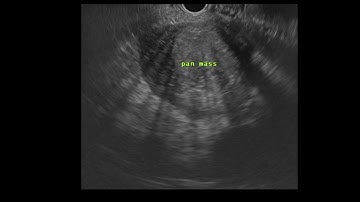

EUS-guided biopsy of lymph node to rule out lymphoma